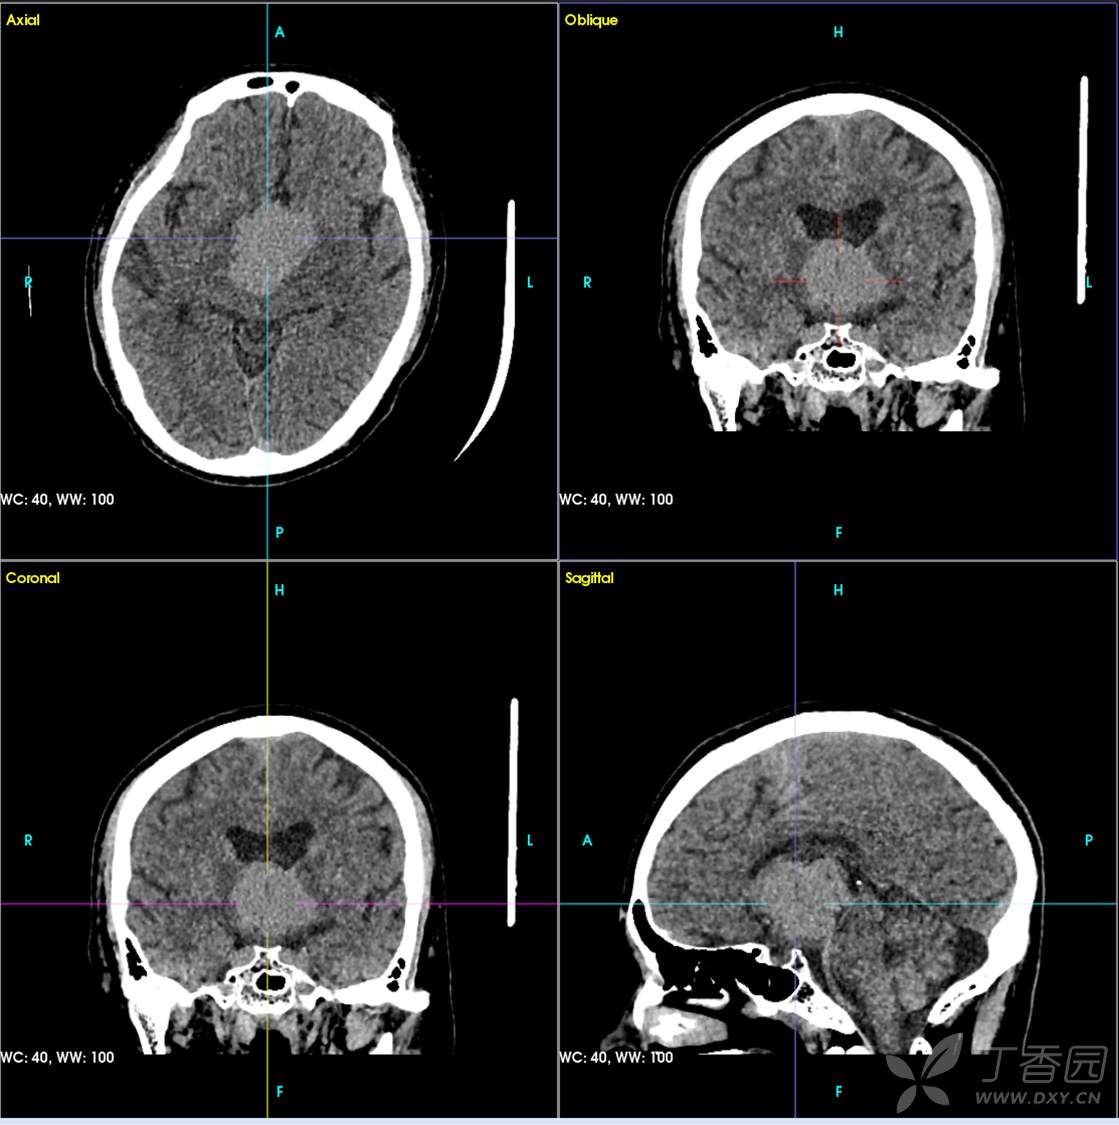

男,44岁,记忆力下降、乏力5月余,多尿3月余,CTMR全,疑难病例,能正确诊断吗?

图像不多,能诊断正确吗?有特征性吗?